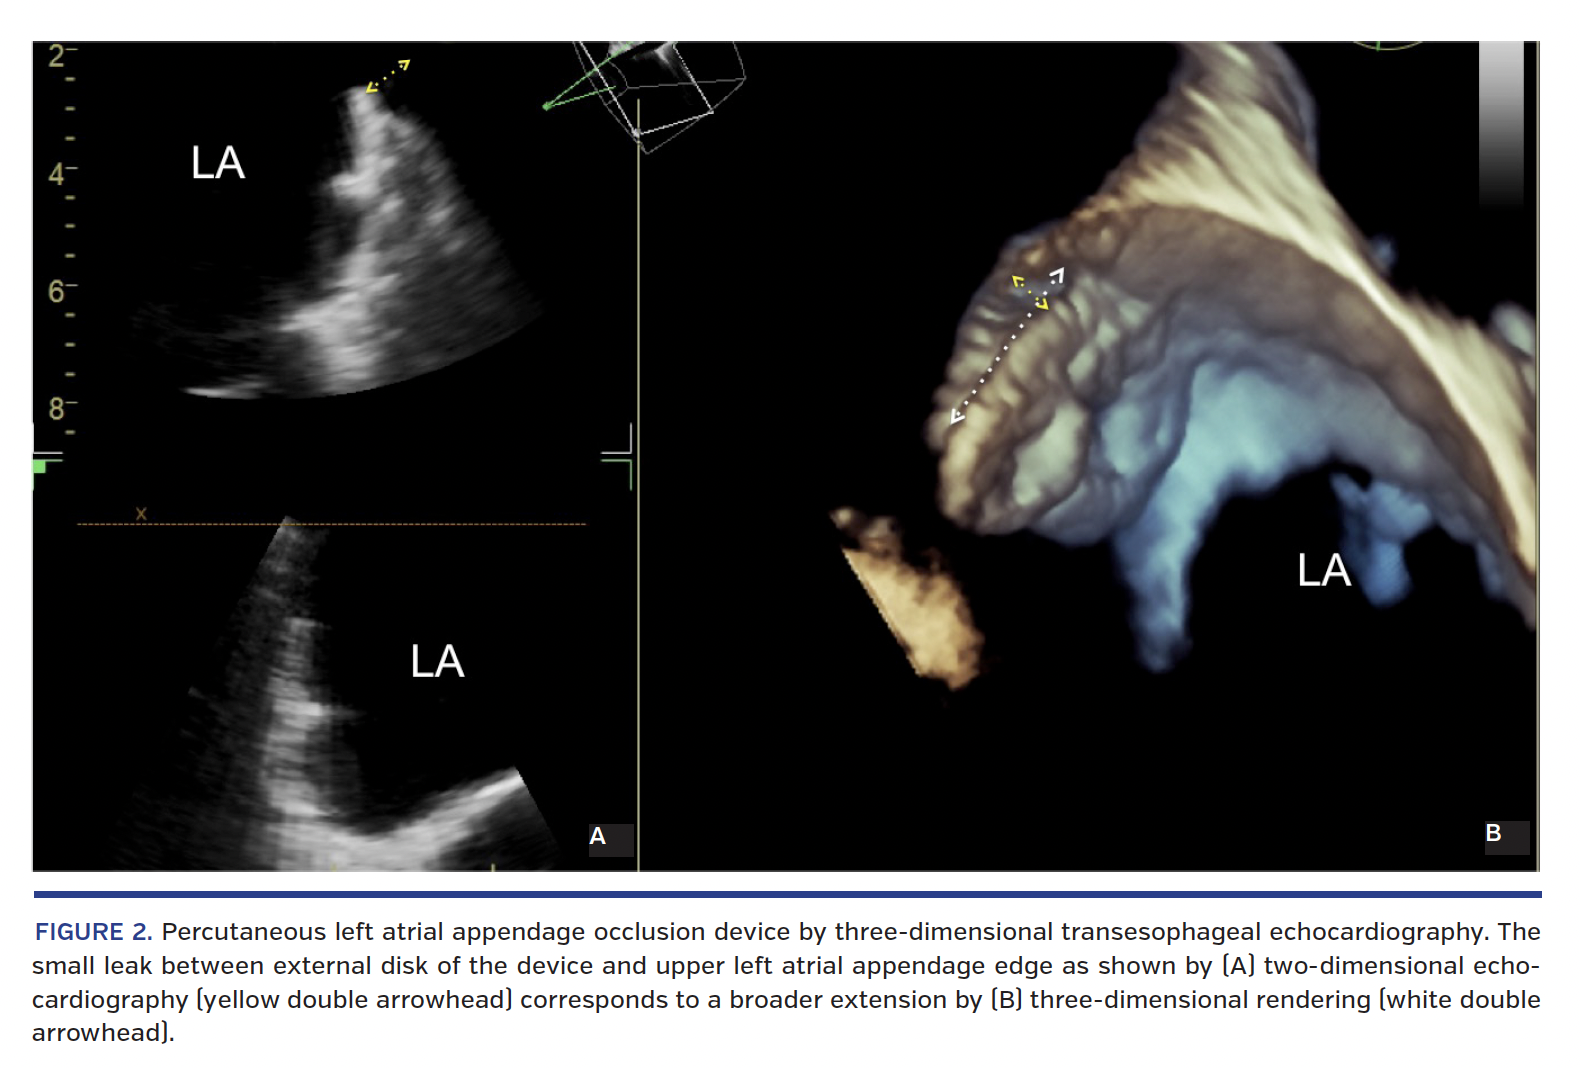

A 73-year-old man with history of coronary artery bypass graft and paroxysmal atrial fibrillation (AF), treated with warfarin, was admitted to our hospital for severe microcytic anemia (hemoglobin, 7.5 g/dL). A low mitotic-index gastrointestinal stromal tumor was discovered and treated conservatively. Contemporary indication was given to elective percutaneous occlusion of the left atrial appendage (LAA) performed with implantation of an Amplatzer Amulet 28 mm (AGA, St. Jude Medical) without complications. Due to the high hemorrhagic risk, only single-antiplatelet treatment was prescribed at discharge for 3 months. Six months later, the patient was admitted to the neurology department for a cardioembolic stroke. The cerebral nuclear magnetic resonance described small acute ischemic areas on the territory of the left mid-cerebral artery. Vascular ultrasonography didn’t reveal any certain cardioembolic source, whereas transesophageal echocardiographic (TEE) study showed a leak in the cranial edge of the device for LAA occlusion, confirmed on color and spectral Doppler (Figure 1) and morphologically detailed on three-dimensional examination (Figure 2).

The presence of a leak around the LAA closure device, implanted for stroke prevention in AF patients who are ineligible for antithrombotic treatment, has been reported as a relatively common finding at both early and delayed follow-up.1 The clinical effect of residual leak is not well defined, but is considered non-significant, particularly if small (peridevice color flow jet width <5 mm by TEE).2 Our case shows that the persistence of LAA patency after percutaneous occlusion in an AF patient could be a direct cause of embolic stroke, in the absence of any other definite cardioembolic source. The application of three-dimensional TEE allows a precise definition of the peridevice leakage (Figure 2).